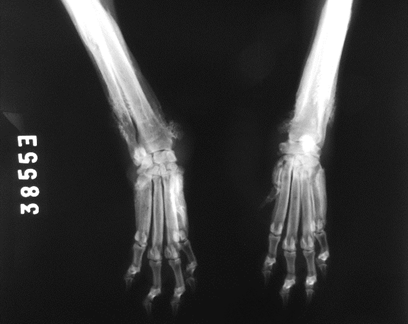

En la evaluación radiológica del tórax no se observaron alteraciones. En las radiografías de los miembros anteriores se encontró inflamación de tejidos blandos a nivel de carpos, reacción perióstica con neoformación ósea de patrón mixtoa nivel de metáfisis distal de cúbito y radio y laminar en diáfisis de metacarpos, con mayor compromiso del miembro anterior derecho. (Figura 2). Las imágenes son compatibles con osteopatía hipertrófica.

Figura 2: Primer radiografía de miembros anteriores. Se observa inflamación de tejidos blandos con neoformación ósea mixta en metacarpos y tercio distal de cubito y radio, compatible con osteopatía hipertrófica.